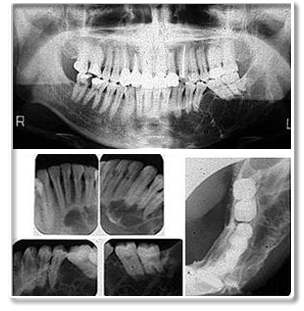

◇ X线摄片示骨质膨胀,有很多大小形状不同、发育不全的影像,或透射度似牙组织的一团影像,影像与正常组织间有一条清晰阴影,为牙瘤的被膜。

X线摄片示骨质膨胀,有很多大小形状不同、发育不全的影像,或透射度似牙组织的一团影像,影像与正常组织间有一条清晰阴影,为牙瘤的被膜。牙源性肿瘤的检查还有病理组织学检查。